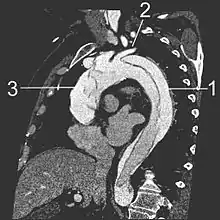

- Le scanner thoracique avec injection de produit de contraste dans le système vasculaire montre un double contraste de l'aorte qui est « coupée » en deux par le « flap ». Il permet de bien en délimiter l'extension. C'est l'examen à réaliser en première intention.